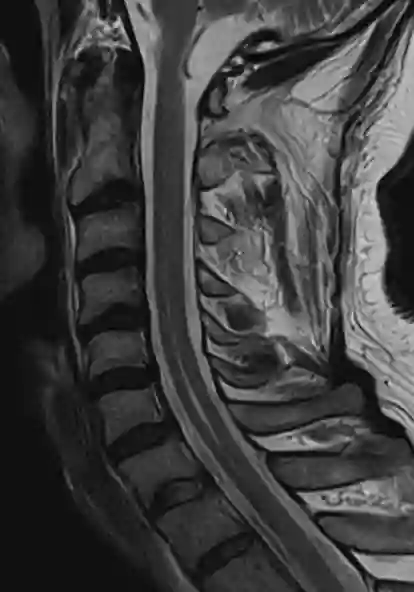

A hydromyelia can be optimally represented in an MR imaging and can be optimally depicted in a T2 weighted MRI sequence.

Hydromyelia

Hydromyelia in a sagittal T2 MRI image of the cervical spinal cord.